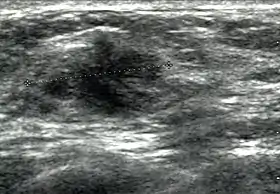

Breast ultrasound

Cancer ultrasound image

Breast ultrasound is a medical imaging technique that uses medical ultrasonography to perform imaging of the breast. It can be performed for either diagnostic or screening purposes[1] and can be used with or without a mammogram.[2] In particular, breast ultrasound may be useful for younger women who have denser fibrous breast tissue that may make mammograms more challenging to interpret.[3][4]